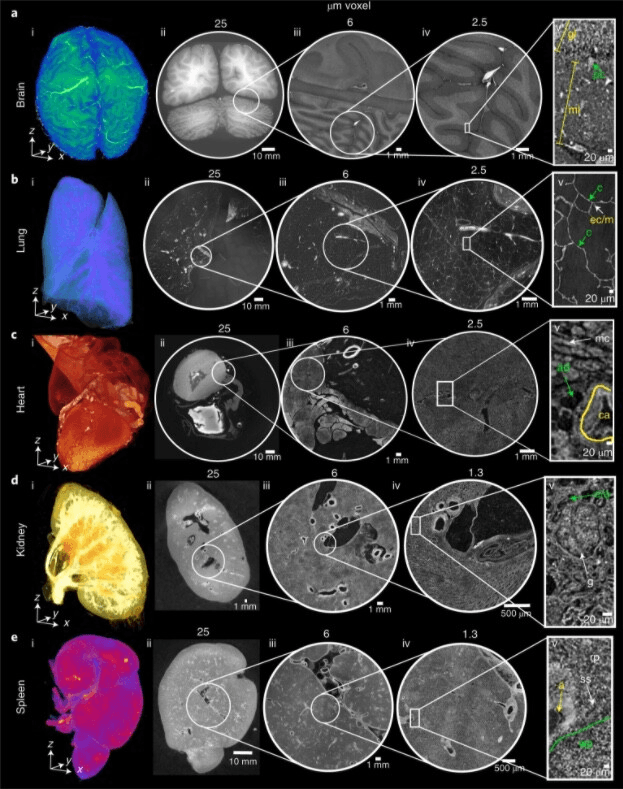

The Human Organ Atlas utilizes Hierarchical Phase-Contrast Tomography (HiP-CT), a cutting-edge imaging technique that bridges the gap between macro and micro-scale medical imaging. While traditional CT scans and MRI can achieve resolution down to just under a millimeter, and histology or electron microscopy can provide sub-micron precision on small tissue samples, HiP-CT uniquely combines these capabilities to image entire organs in 3D with micrometer-level detail.

According to Peter Lee, head of the project, "HiP-CT brings these scales together in 3D, imaging whole organs to provide new insights into our biological structure." This technology enables healthcare professionals to visualize complete organ systems with cellular-level detail, revolutionizing diagnostic capabilities and treatment planning processes.

Paul Tafforeau, ESRF scientist, explains: "This technology allows us to see in 3D the incredibly small vessels inside an entire human organ, which allows us to distinguish in 3D a blood vessel from the surrounding tissue and even observe some specific cells." This level of detail enables healthcare providers to identify disease patterns and vascular changes that were previously invisible with conventional imaging methods.